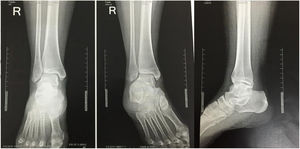

Materiales y MétodosSe realizó un ensayo auto-controlado, aleatorizado, doble ciego, multicéntrico, mediante la aplicación de encuestas en tres países a ortopedistas generales, subespecialistas en cirugía de pie y tobillo y residentes de ortopedia y traumatología. Se estableció el criterio de aleatorización simple mediante la presencia de los encuestados en los simposios de pie y tobillo en la ciudad de Guayaquil en el marco del congreso Ecuatoriano de Ortopedia y Traumatología, En la ciudad de Cali en el marco del curso nacional del Pie y Tobillo de la sociedad Colombiana de Cirugía Ortopédica y Traumatología y en la ciudad de Cancún en el marco del Congreso mexicano de Ortopedia y Traumatología de la FEMECOT, estableciéndose como criterio de inclusión estar en disposición de evaluar los casos clínicos y realizar la encuesta independientemente de su grado de entrenamiento o años de experiencia. Se entregaron cuatro casos de fracturas de tobillo Webber B de características quirúrgicas por sus mediciones radiológicas con desenlaces conocidos por los autores Senior (Eduardo Reina, Juan Manuel Herrera, Carlos Ramirez, Bosco Mendoza y Victor Toledo) como se observa en la figura 1.

En el caso número 1 se estableció como criterio quirúrgico la diferencia de el ángulo talocrural de 6° y la línea de shenton con una incongruencia de 3mm en el lado fracturado figuras 2 y 3